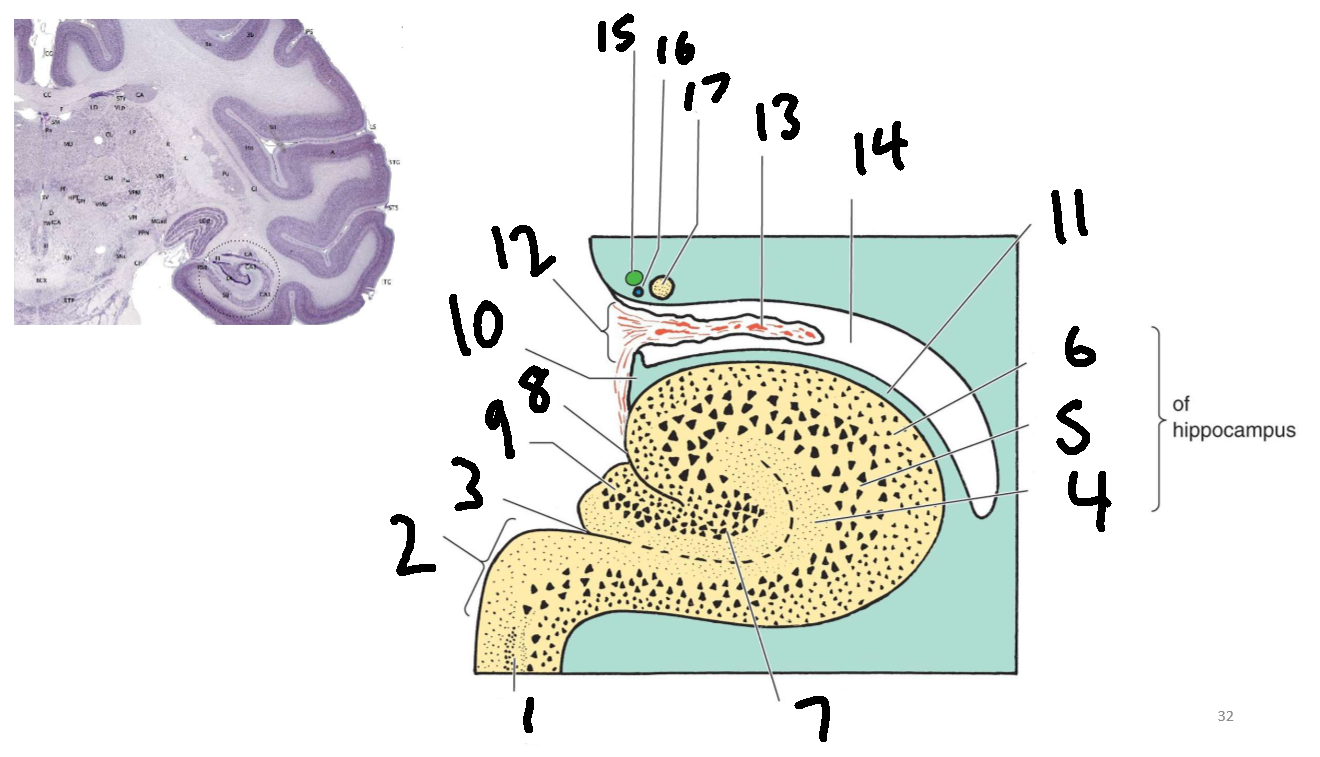

What structure is this?

hippocampus

What is 1?

hippocampus

What is 2?

rhinal sulcus

What is 3?

lateral ventricle

What is 4?

thalamus

What is 5?

entorhinal cortex

What is 6?

perirhinal cortex

What is 7?

parahippocampal cortex

What is 1?

gyrus dentatus

What is 2?

cornu ammonis

What is 3?

fimbria

What is 3’?

alveus

What is the arrow pointing to?

happicampal sulcus

What is ca1, ca2, ca3 and ca4?

fields of cornu ammonis

What is 4?

tela choroidea

What is 5?

stria terminalis

What is 6?

tail of caudate nucleus

What is 7?

temporal horn of lateral ventricle

What is 8?

collateral eminence

What is 9?

collateral sulcus

What is 10?

parahippocampal

What is 11?

entorhinal area

What is 12?

subiculum

What is 13?

lateral geniculate body